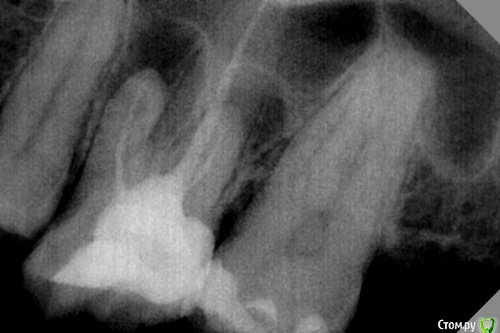

DmitrySH Опубликовано 6 сентября, 2016 Поделиться Опубликовано 6 сентября, 2016 С оптикой такие вещи легко закрываются. Да и без оптики можно. Это же не в средней/апикальной части Ссылка на комментарий

red_butler Опубликовано 8 сентября, 2016 Поделиться Опубликовано 8 сентября, 2016 без коффера прогноз перфорации плохой 1 Ссылка на комментарий

Ker Опубликовано 15 сентября, 2016 Поделиться Опубликовано 15 сентября, 2016 Доктор, думаю вы не видели устье глазами. Если не видите устье - пилите пока не увидите, особенно при перелечивании. Лучше немного твердых тканей убрать чем сделать перфо, особенно при перелечивании таких зубов, когда терять уже не слишком много. Ссылка на комментарий

Fred Опубликовано 22 сентября, 2016 Поделиться Опубликовано 22 сентября, 2016 Фатальная триада: ноу коффер, ноу МБ2 и перфа. Зуб погиб Ссылка на комментарий